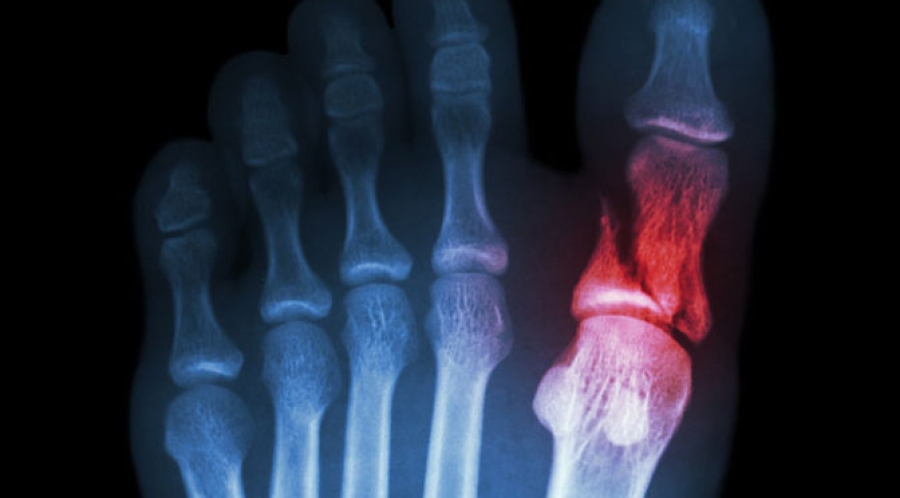

Product Name: Cracked toe bone shop

Broken Toes Fractured Toe Pain Foot Health Facts Foot Health shop, Toe Fractures Metatarsal Fractures Broken Toe Broken Foot shop, Toe and Forefoot Fractures OrthoInfo AAOS shop, Broken Toe Fractured Toe Causes Symptoms Treatment shop, Clinical Practice Guidelines Toe Fractures Emergency Department shop, How to Treat a Broken Toe A Podiatrists Guide shop, Common Symptoms and Treatment of a Fractured Toe shop, Broken toe Treatments symptoms pictures and healing time shop, Foot Fractures Injuries and Poisoning Merck Manuals Consumer shop, Broken toe Wikipedia shop, Toe and Forefoot Fractures OrthoInfo AAOS shop, Broken Toes Tennessee Ankle Foot Centers of America shop, Metatarsal Fracture Orthopaedic Trauma Association OTA shop, Great big toe fracture or injury CUH shop, Treating a Toe Fracture How to Handle a Broken Toe shop, Symptoms of Broken Toes District Foot and Ankle PLLC District shop, Broken Big Toe Causes Symptoms Diagnosis and Treatments The shop, Broken Toe Symptoms and What to Do About It shop, Do I Have a Broken Toe Cone Health shop, Broken Pinky Toe Signs Symptoms Canyon Oaks Foot Ankle shop, Toe and Forefoot Fractures OrthoInfo AAOS shop, NYC Podiatry Center of Excellence Broken Foot Toe Ankle shop, Here s What Happens When you Don t Treat a Broken Toe shop, Traditional Chinese Medicine Case Report Broken Big Toe Alina shop, Picture of Broken Toe Picture Image on RxList shop, Broken toe Wikipedia shop, Broken toe bone X ray Stock Image C007 1964 Science Photo shop, How To Treat A Broken Toe AccidentClaimsAdvice shop, What Can Happen to an Untreated Broken Toe Podiatrist Foot shop, How Do I Know If My Toe is Broken RNV Podiatry shop, Are Broken Toes a Serious Condition shop, Toe Fractures Advanced Orthopaedics Sports Medicine shop, Broken pinky toe Symptoms treatment and other conditions shop, When to See a Doctor for a Broken Toe shop, Should I go to the Hospital for a Broken Toe Dr. Nicholas shop, Broken Bones Fractures in Foot Feet For Life Bessemer AL shop, Toe Fracture Treatment Protective Footwear Orthotics Plus shop, What is a Great Toe Fracture How to Manage This Injury shop, Sprained Big Toe vs. Broken Big Toe Causes Symptoms How to Treat shop, What are the Treatments for Metatarsal Fractures Dr. Elton shop, Metatarsal Stress Fracture A Small Crack at the Metatarsal Bone shop, Traditional Chinese Medicine Case Report Broken Big Toe Alina shop, Dr. Mehmet Oz I fractured a bone in my foot after Facebook shop, Toe and Forefoot Fractures OrthoInfo AAOS shop, Broken toe Treatments symptoms pictures and healing time shop, Dog Broken Toe Expert Answers from a Vet Dr. Buzby s ToeGrips shop, Running with a toe fracture. Is it safe Dr. Nick s Running Blog shop, What Can You Do for A Broken Toe GoodRx shop, Fractured Toe in Kingston WA shop, Fractured toe X ray Stock Image C056 4219 Science Photo Library shop.

Cracked toe bone shop